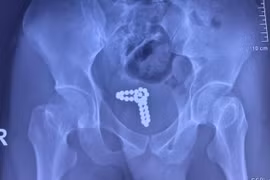

“Tự sướng” bằng chuỗi bi kim loại, nam thanh niên nhập viện

(GLO) - Ngày 28-2, thông tin từ Bệnh viện Nhân Dân 115 cho biết vừa cấp cứu can thiệp cho bệnh nhân nam N.B.T. (SN 2001, ngụ tại TP. HCM) trong tình trạng tiểu ra máu do bị dị vật rơi vào niệu đạo rất hy hữu.